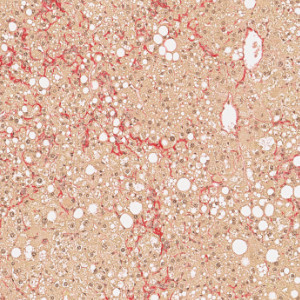

Figure 7

PSR stained liver tissue with fibrosis.

Figure 8

PSR stained liver tissue with identified bridging fibrosis shown in grey.